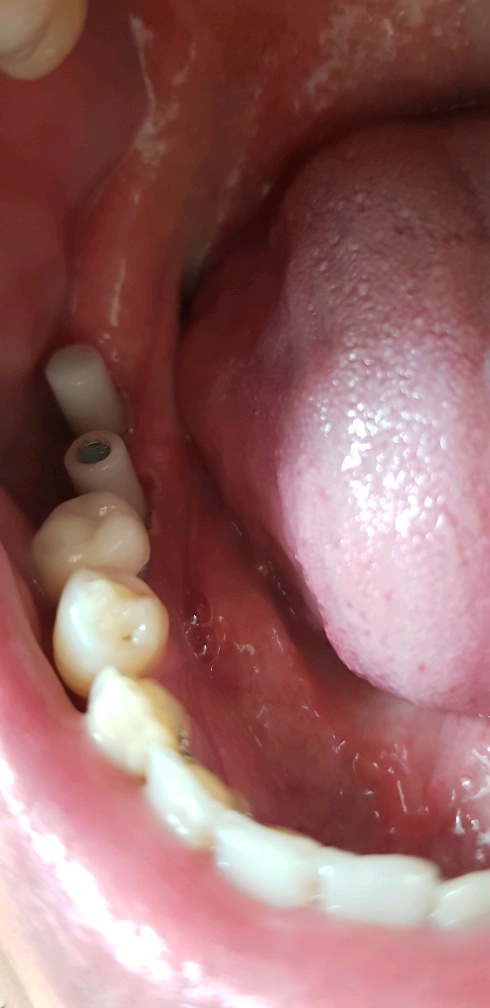

이건 2번째 방문한 오늘 박아놓은 임플란트다.

다음주 화요일에는 정말 치아를 올린다고 한다.